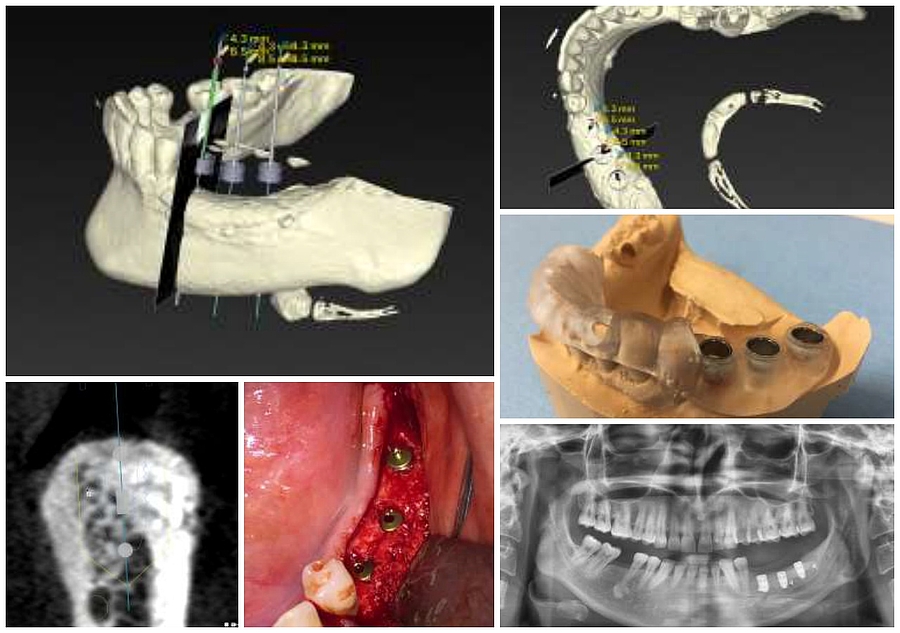

1 + 2: Planung der Implantatpositionierung anhand eines dreidimensionalen DVT-Datensatzes und eines digitalisierten

Abdrucks

3: Präoperativ gefertigte Schablone zur Übertragung

4: Exakte Implantatpositionierung im aufgebauten Knochen der zuvor geplanten Implantatposition

5: Darstellung der inserierten Implantate. Durch den Knochenaufbau konnten die Implantate stabil und allseits von Knochen

umgeben platziert werden

6: Das postoperative Röntgenbild zeigt die Lage der Impantate im Unterkieferseitenzahnbereich links